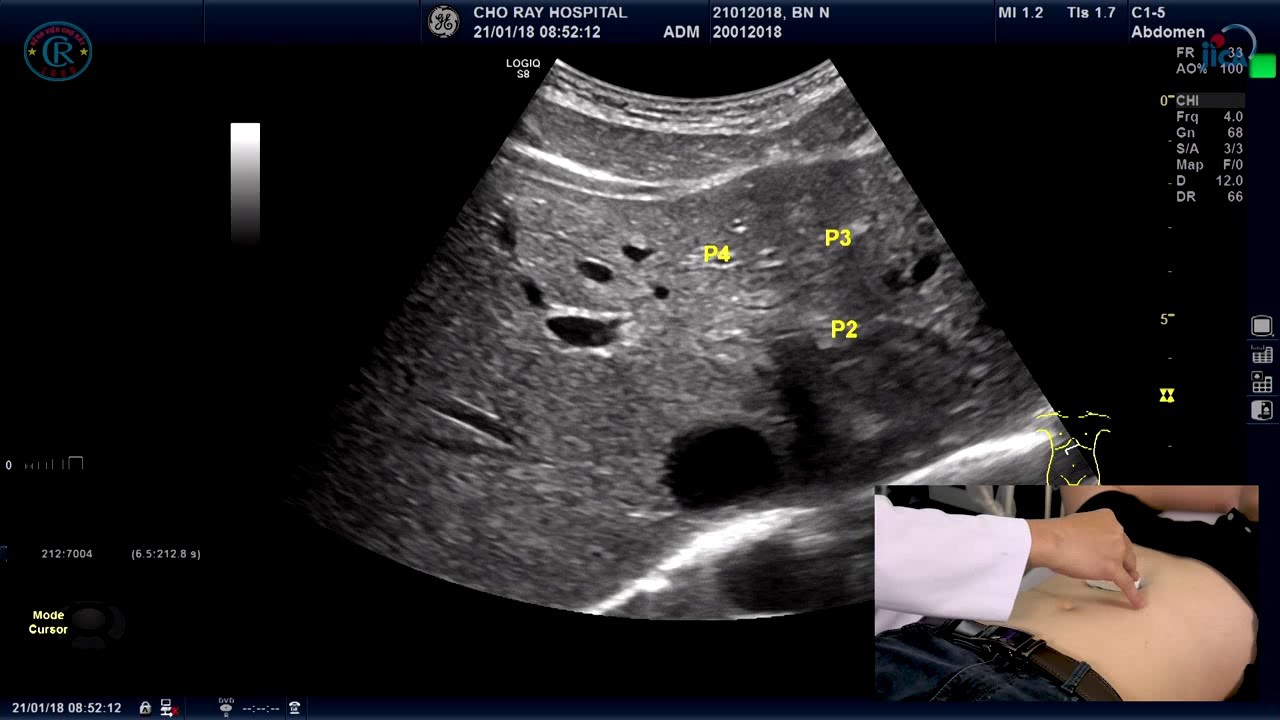

Siêu âm ổ bụng tổng quát là kỹ thuật chẩn đoán hình ảnh phổ biến. Đây là một kỹ thuật chẩn đoán hình ảnh thường được chỉ định để kiểm tra sức khỏe tổng quát hoặc tìm nguyên nhân của các triệu chứng đau, sưng hoặc nhiễm trùng ổ bụng.

Siêu âm ổ bụng giúp kiểm tra các cơ quan bên trong vùng bụng và vùng chậu: gan, thận, lách, mật, tụy, dạ dày, ruột, niệu quản, bàng quang, tuyến tiền liệt, buồng trứng, tử cung…

Qua hình ảnh siêu âm, bác sĩ có thể phát hiện và chẩn đoán các bệnh lý như:

- Bệnh ở gan: Siêu âm giúp phát hiện và chẩn đoán bất thường bẩm sinh, viêm gan do virus, nhiễm trùng gan, gan nhiễm mỡ, xơ gan, u gan lành tính và ác tính…

- Bệnh ở lách: Siêu âm giúp phát hiện và chẩn đoán lách to, nang, áp xe, chấn thương…

- Bệnh ở túi mật: Siêu âm thấy sỏi, viêm, áp xe túi mật, dày thành túi mật, xẹp lòng túi mật, u túi mật…

- Bệnh ở đường mật: Siêu âm thấy tắc nghẽn, viêm, sỏi, u đường mật, ký sinh trùng đường mật…

- Bệnh ở tuyến tụy: Siêu âm thấy viêm tụy cấp và mạn tính, u tụy…

- Bệnh ở đường tiêu hóa: Siêu âm giúp phát hiện và chẩn đoán ung thư đường tiêu hóa, bệnh Crohn, viêm ruột thừa, viêm túi thừa, tắc ống tiêu hóa, viêm đại tràng, viêm manh tràng, dị vật trong lòng ống tiêu hóa…

- Bệnh ở đường tiết niệu: Siêu âm giúp phát hiện và chẩn đoán viêm đài bể thận, áp xe thận và quanh thận, lao thận, viêm bàng quang; sỏi thận, sỏi niệu quản, sỏi bàng quang; khối u đường tiết niệu…